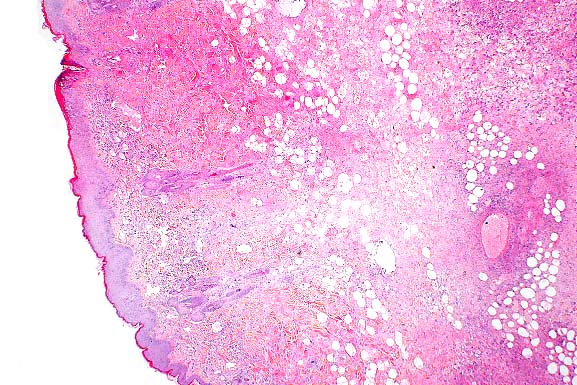

- Case 24-1. Low power view has necrosis and inflammation

of nasal mucosa and thrombosis of nasal vessels. Larger thrombus

demonstrates lines of Zahn (layers of fibrin, wbcs, platelets,

RBCs, etc). Higher power view of vessel wall infiltrated and

replaced by mostly degenerate neutrophils and fibrin. Lines of

Zahn are seen more clearly on the left.